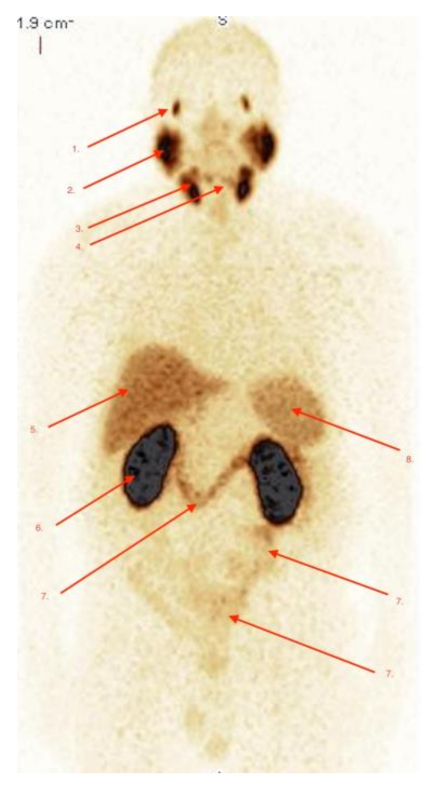

2.3. Imaging Studies

2.4. Detection of Active Pathology in Patients